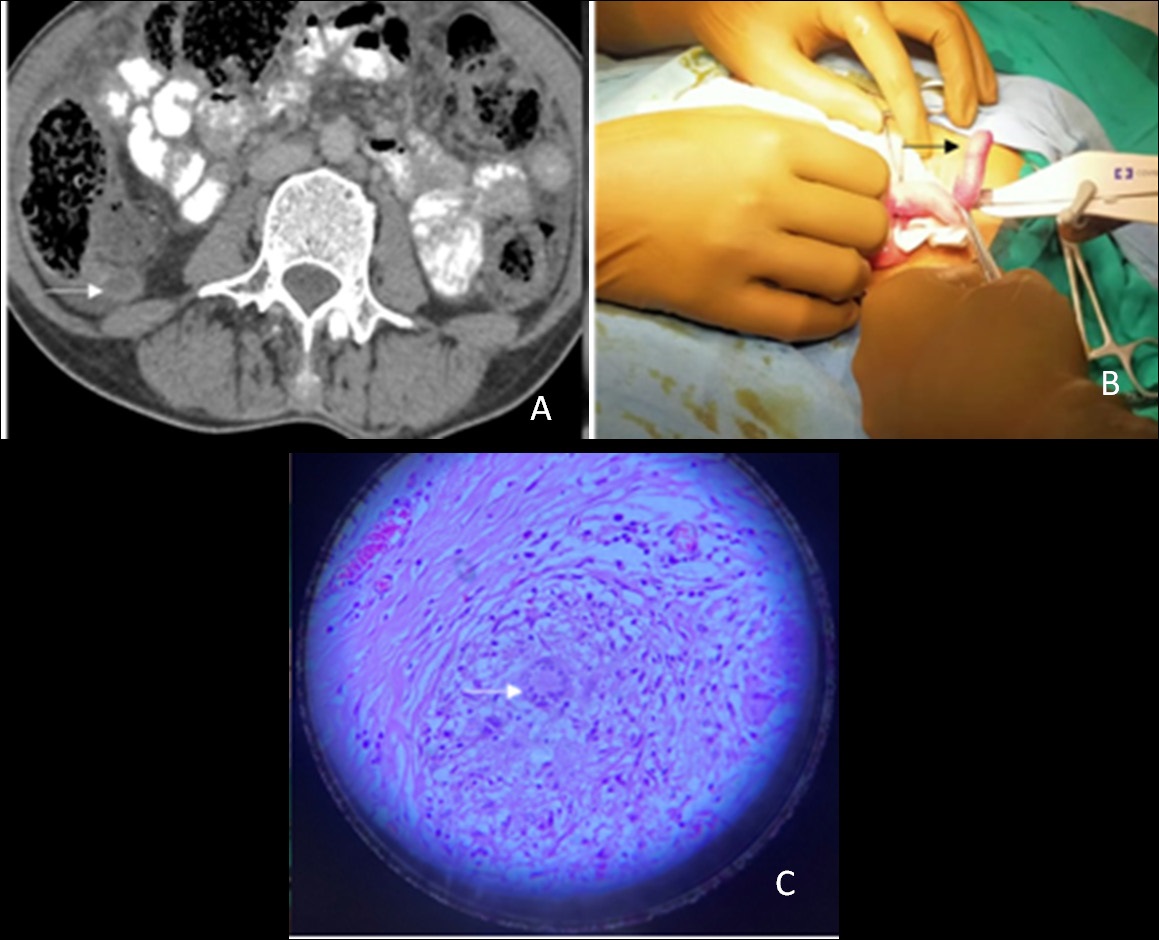

Tubercular appendicitis

Tubercular appendicitis is usually mistaken as bacterial appendicitis or any other inflammatory disease. The infection can lead to perforation; therefore, it is advisable to remove the appendix in all abdominal tuberculosis patients undergoing surgery for any reason (Figure 6A,6B,6C).

Figure 6: A 37-year-old female presented with severe pain in the right iliac fossa. On clinical examination she had fever and tachycardia with guarding and rigidity in the right iliac fossa. (A) The patient underwent contrast-enhanced computed tomography (CT) scan of the abdomen, which revealed a distended retrocaecal appendix with thick enhancing walls (white arrow) and adjacent fat stranding. (B) The patient underwent appendicectomy and a reddish swollen angry-looking appendix was found intra-operatively (black arrow). The patient had uncomplicated post-operative period. (C) On histopathology, there were multiple granulomatous lesions and areas of caseous necrosis surrounded by Langerhan’s giant cells and epithelioid cells (white arrow). The patient started on anti-tubercular drugs and kept on follow-up. She is doing fine till the last follow up. Acute tubercular appendicitis is very rare condition. A contrast-enhanced CT scan is the ideal imaging modality for the evaluation of such cases.